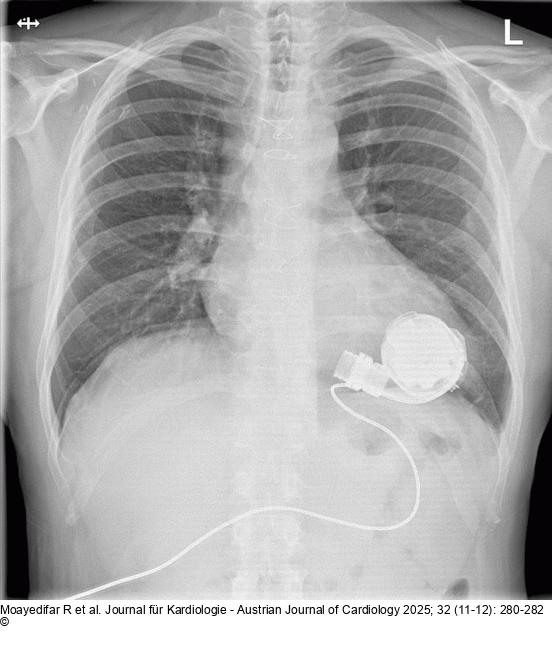

Abbildung 1: Thoraxröntgen Postoperatives Thoraxröntgen des Patienten |